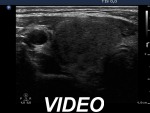

Ultrasonography: There were many hypoechogenic areas with blurred borders within both lobes. The vascularization was decreased.